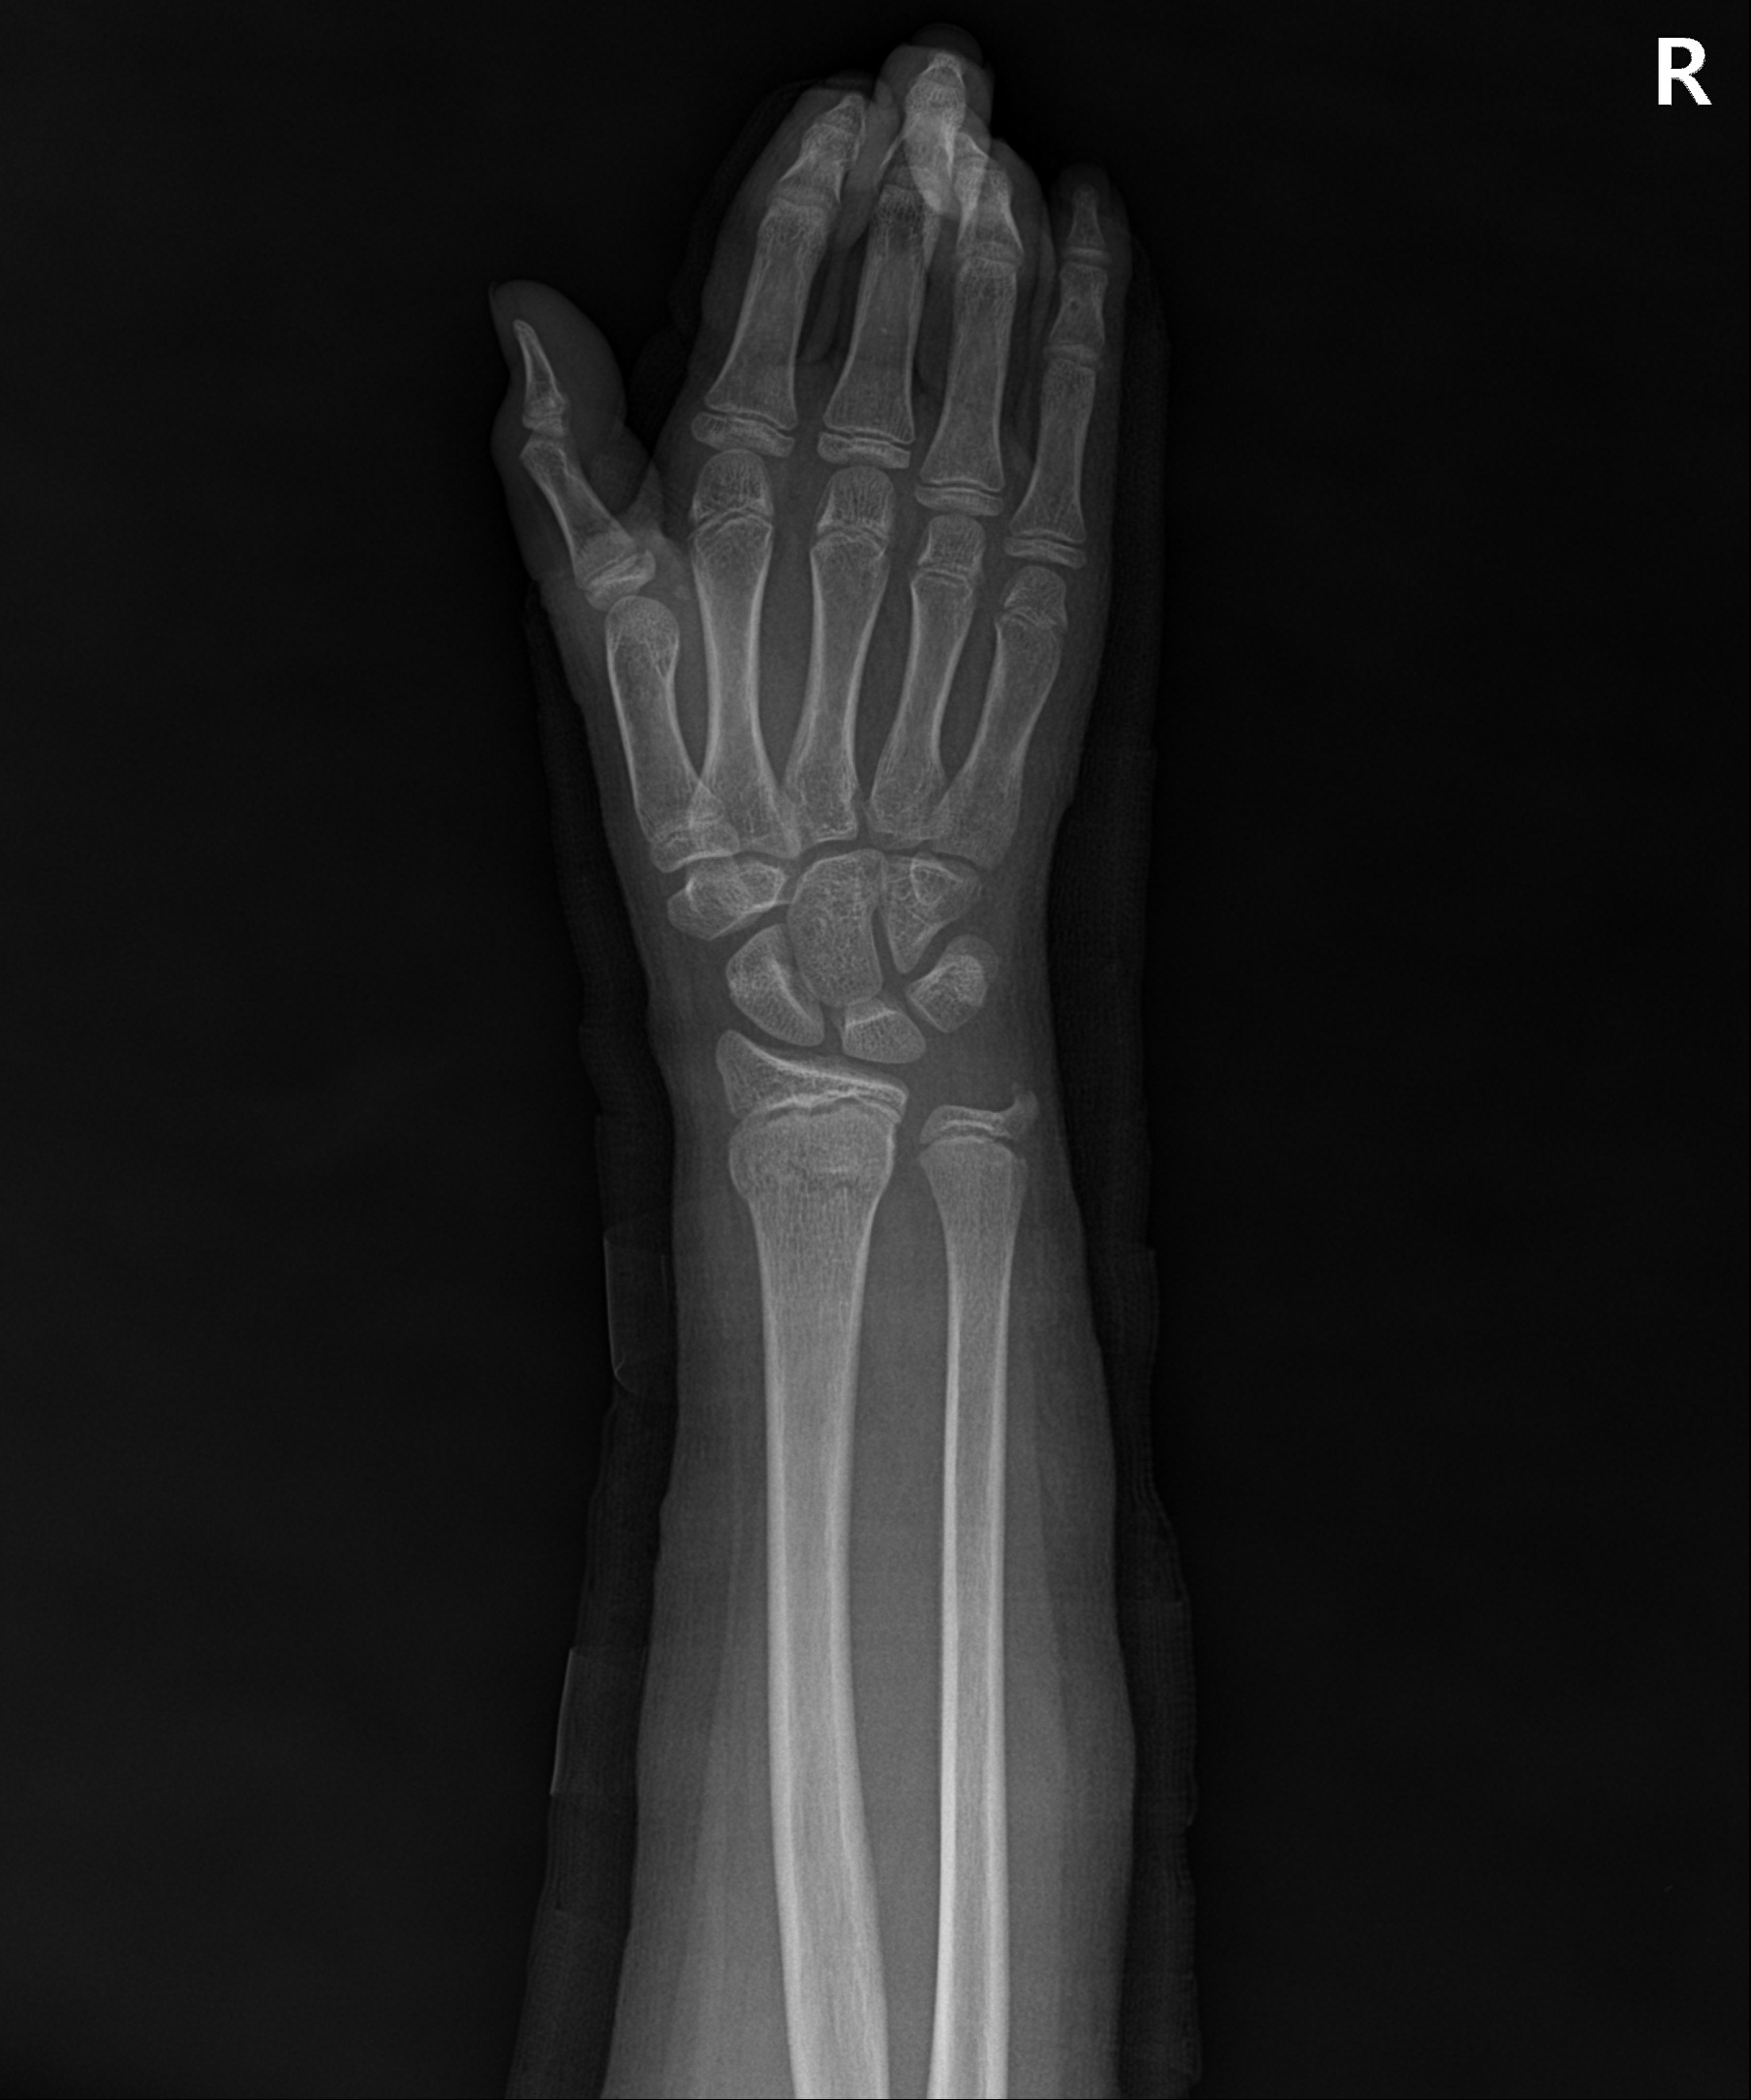

손목 골절 및 손가락 골절

대부분 손을 짚고 넘어지면서 발생하는 골절이고 다치면서 손등 쪽 뼈가 심하게 분쇄되는 경우가 많습니다.

골절 초기나 아니면 지연성으로 골절편이 손등 쪽으로 휘어져 변형이 발생하기 쉽습니다.

손목&손가락 골절에서 발생하는 문제점

□ 골절을 유합 시키기 위해 장기간 깁스를 할 경우 손목 관절이나 손가락 강직 발생

□ 손목 관절을 정확히 정복하지 못할 경우 외상성 관절염 발생 위험 높음

손목 골절

2023.01.04

2023.03.20